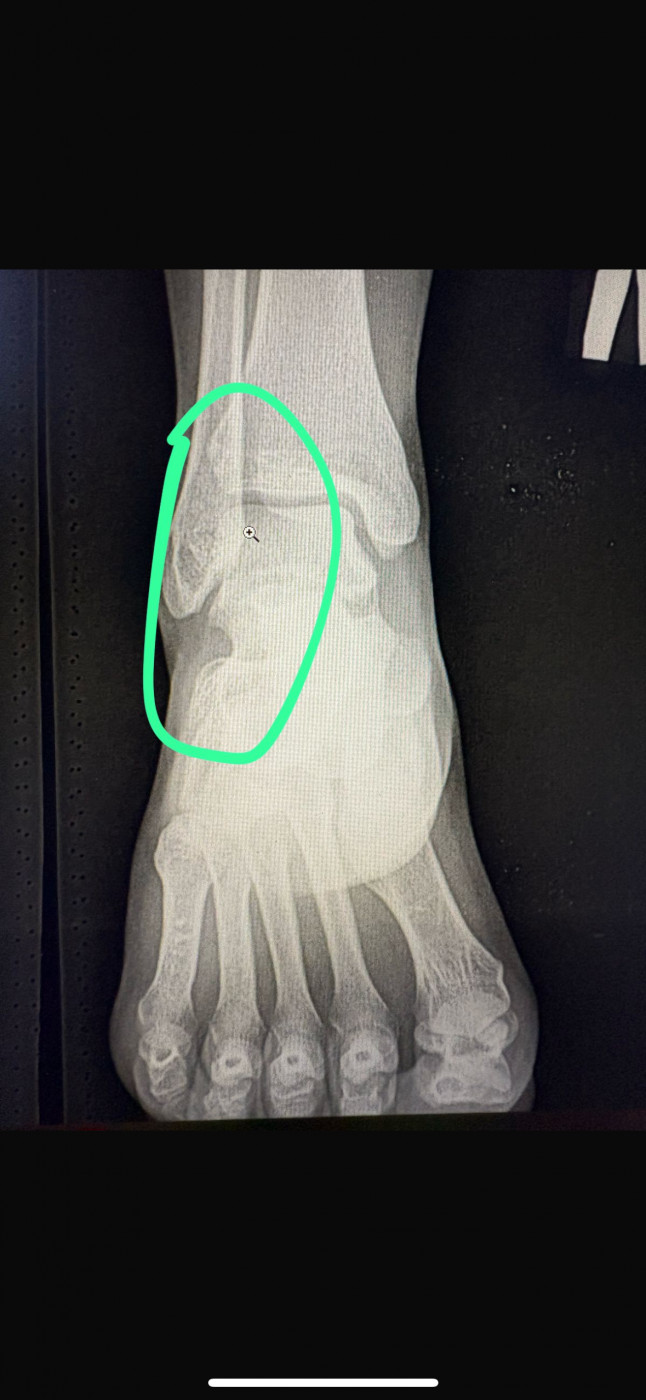

На сколько серьезный диагноз , какие дальнейшие действи нужно совершать ?   1 ответ

Боли в ноге голеностоп, болевые ощущения при ходьбе , ноющие боли , была сломана нога поставили пластину , пластину не убирали спустя 13 лет , обратились к врачу . Женщина, 47 лет .